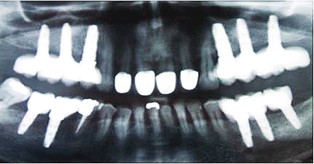

Los implantes dentales son estructuras metálicas que se anclan al hueso maxilar o mandibular, y sobre las que se fijan prótesis dentales. El implante dental es por tanto la raíz del nuevo diente, y la prótesis dental que se pone encima es la nueva corona del diente.

El excelente resultado de estos tratamientos, unido a las mejoras en el diseño y composición química y física de los implantes, ha hecho que actualmente los implantes dentales hayan sustituido a los puentes sobre dientes en casi todas las situaciones clínicas. Es decir, los implantes no se usan sólo en casos muy difíciles, o que son muy complicados de resolver con prótesis convencionales. Ahora los implantes se usan (y es donde más éxito tienen) en los casos "fáciles", en los que hay ausencia de uno o unos pocos dientes, y hay abundante hueso en los maxilares.